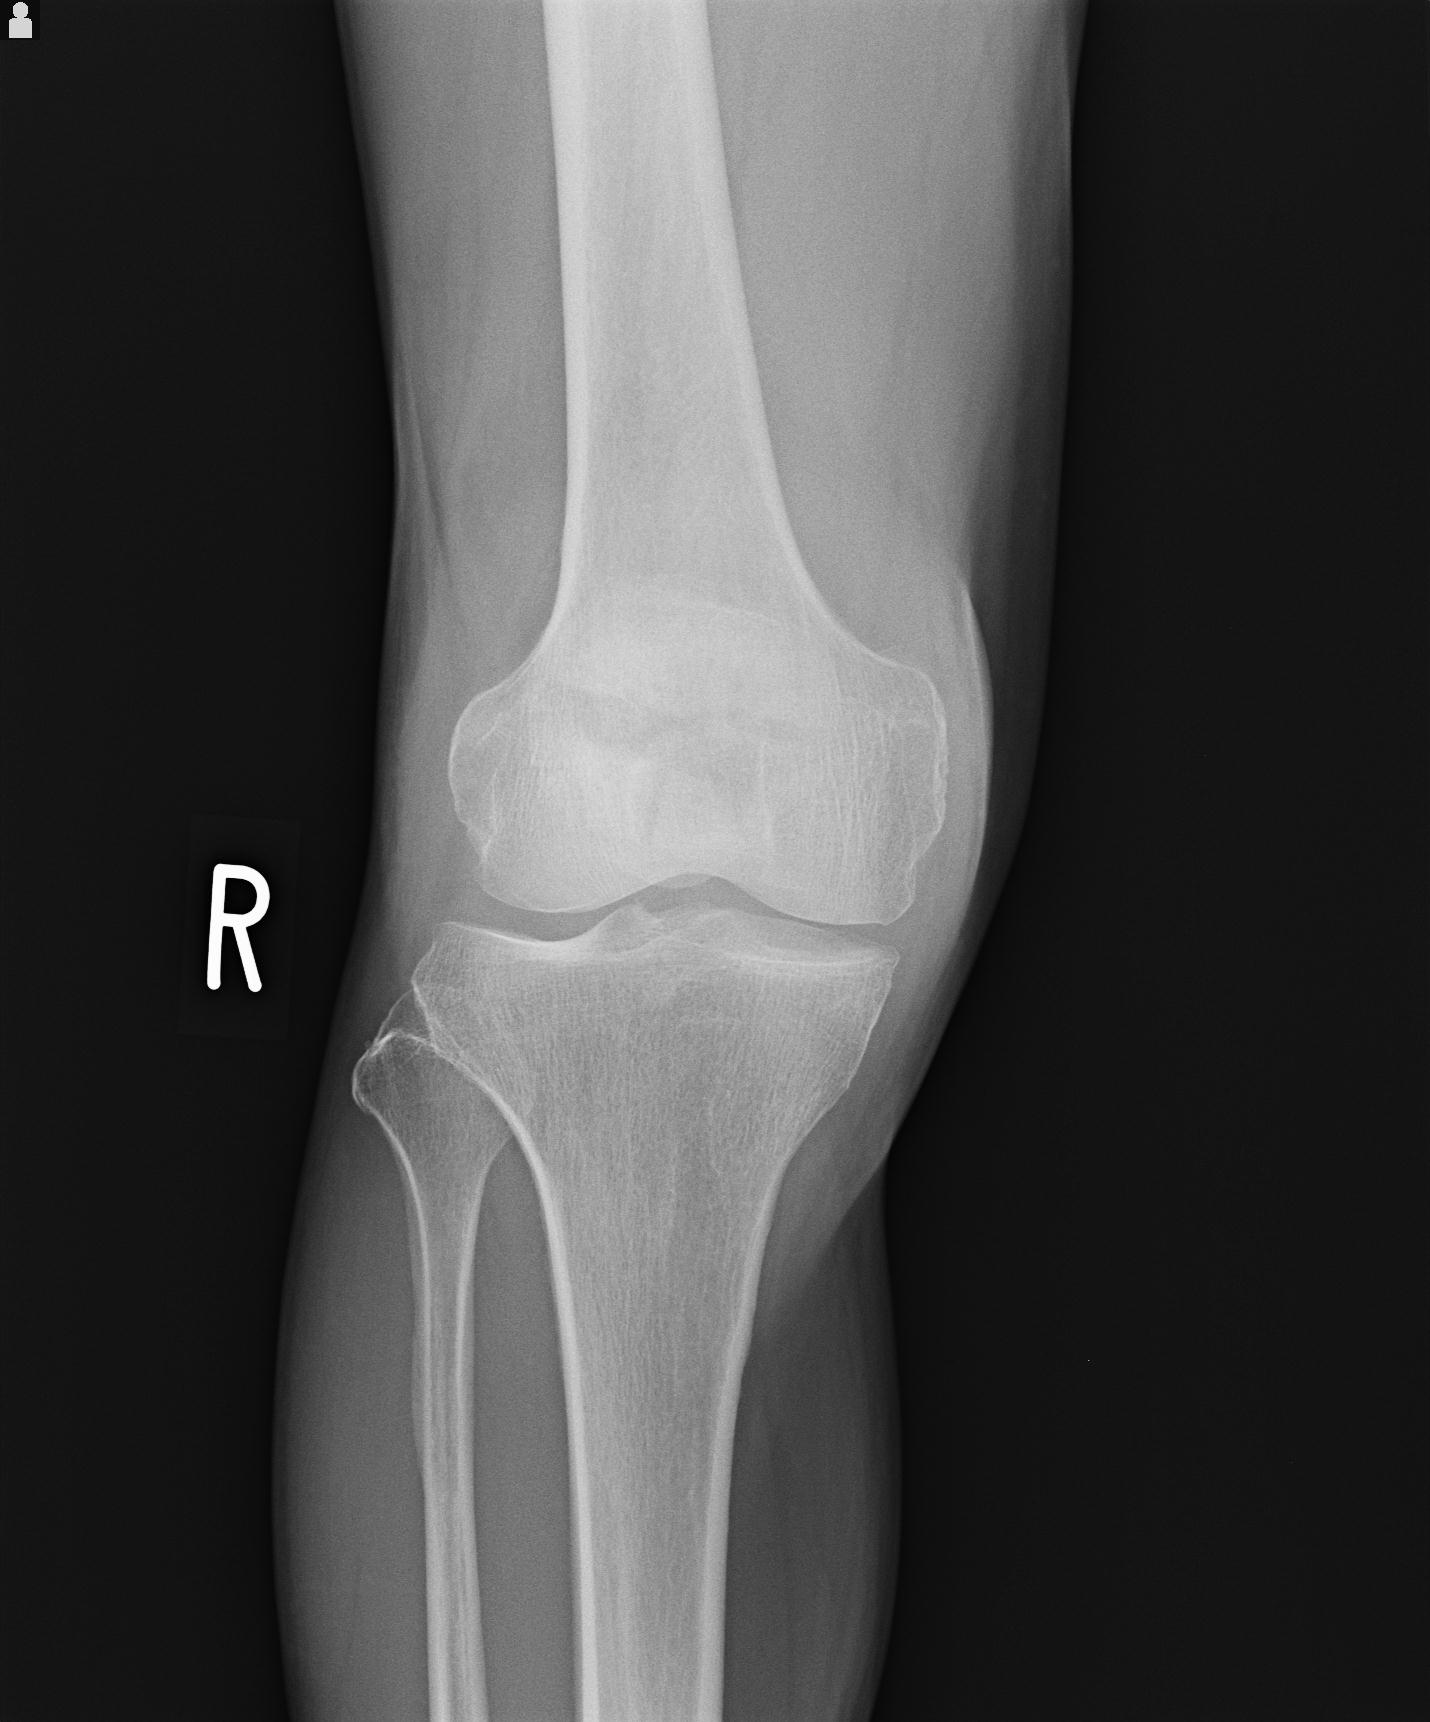

91983 11/16 左膝 2R 11/18 2R 55歳男性 脛骨骨切り術